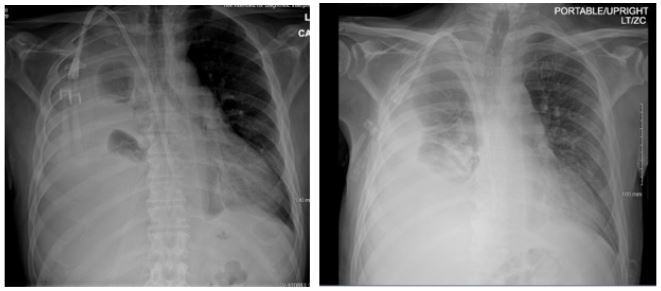

Patient presented with elevated blood pressure at 174/88. BMP was significant for Na 133, K 4.6, BUN 29, Cr 5.3. CMP is significant for Albumin 2.5. CBC was significant for Hb 8.7, Hct 25.0. D-dimer was found elevated at 4,670. PT and INR were normal. ABG significant for pH 7.52, pCO2 31.4, HCO3 25.3. A chest x-ray on admission demonstrated a large right-sided pleural effusion, contributing to significant compressive atelectasis of the right lung and leftward deviation of the mediastinal structures. Thoracentesis was performed, which demonstrated blood- tinged serosanguinous fluid. Transthoracic echocardiogram demonstrated EF 60-65%, LV diastolic dysfunction, with trace mitral and tricuspid regurgitation, and was negative for pericardial effusion. CT Chest demonstrated a large volume right-sided pleural effusion without pneumothorax, with extensive progressive atelectasis throughout the right lung. There was also a trace left-sided pleural effusion and pleural thickening with round atelectasis in the posterior left lower lobe, as well as minimal interstitial edema in the left lung. A chest tube was placed with consistent drainage throughout admission. Repeat chest x-rays continued to demonstrate pleural effusion. Thoracotomy, decortication, and pleurodesis were performed with Video-Assisted Thoracoscopic Surgery (VATS), with significant improvement of symptoms. The pleural fluid biopsy was negative for malignancy and revealed fibrocollagenous tissue with chronic inflammation and a few reactive epithelial cells. Thorough review of the patient’s medication list led to suspicion that the patient’s 50 mg Hydralazine three times a day may be the offending agent. Anti-histone antibody titers were found to be elevated at 3.7. Free Kappa and Lambda light chains were elevated. Antinuclear Antibody (ANA) titers were found to be negative. Hydralazine was discontinued, and after chest tube removal and improved chest x-ray, the patient was discharged home. It was recommended that the patient follow up with their primary care provider and rheumatologist.

Figure 3: Chest radiographs obtained post-VATS and prior to discharge. Compared to initial presentation, there is marked interval improvement with resolution of the large right pleural effusion and re- expansion of the right lung.